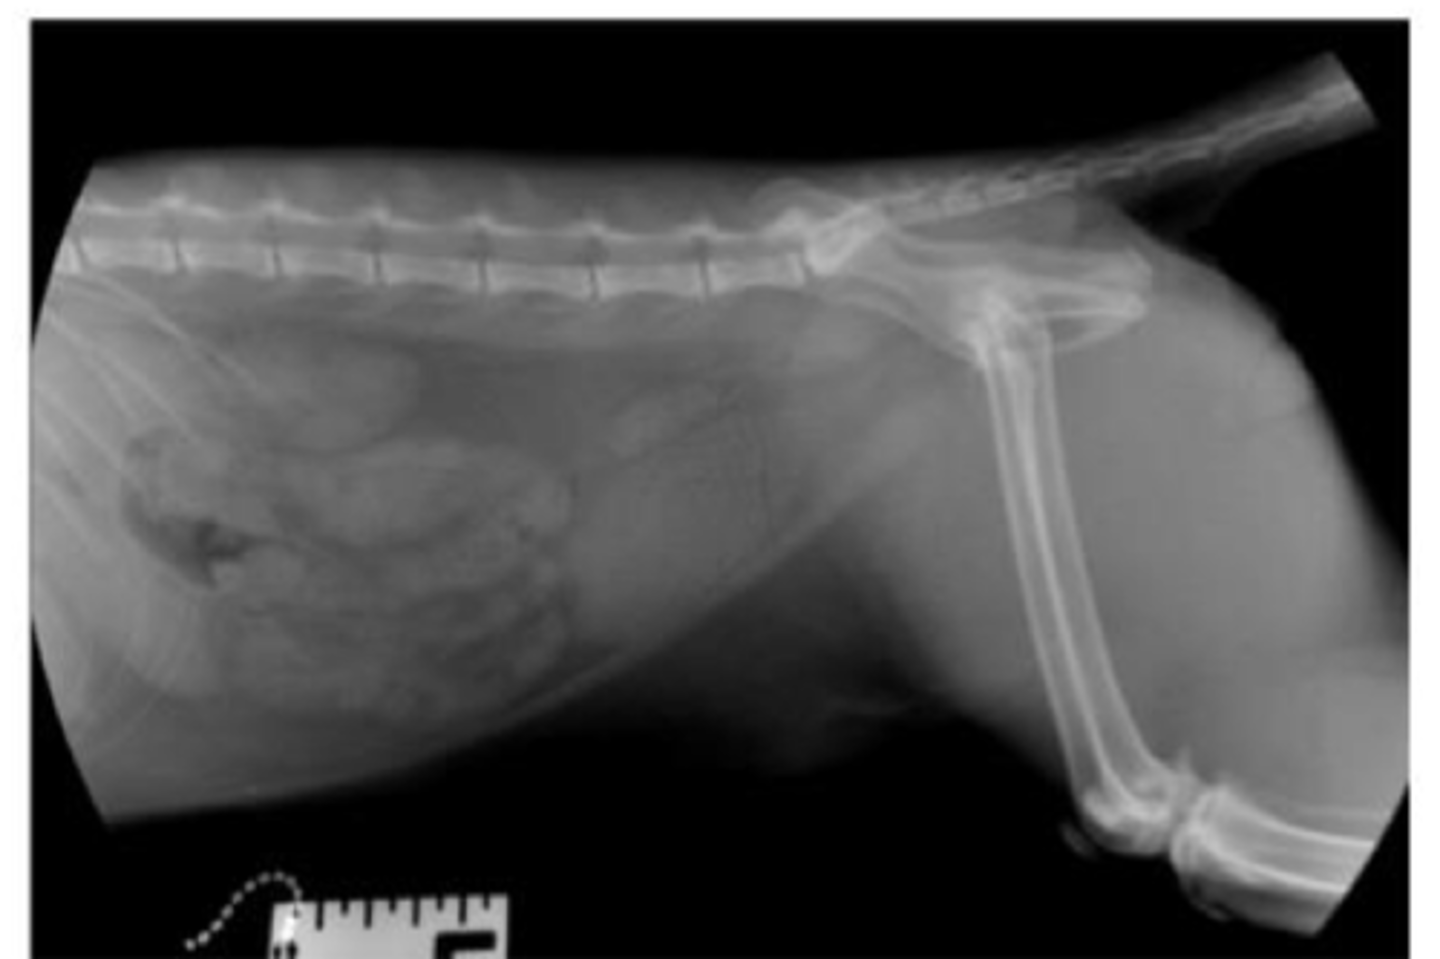

Lateral of the abdomen

Ventrodorsal of the abdomen

Describe the normal radiographic anatomy of canine kidneys

Number: 2

Location: retroperitoneal space

- Right: cranial, renal fossa, T13

- Left: More mobile, L1-L3, more caudal

Shape: oval (bean)

Margination: smooth

Opacity: soft tissue

Size: 2.5-3.5x L2 vertebra